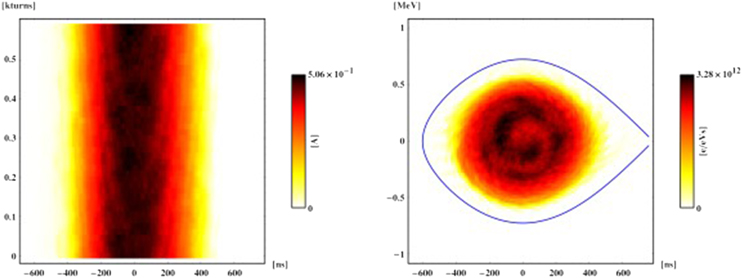

One such approach is phase-space tomography [18], a hybrid algorithm that was originally pioneered at CERN to image particle beams circulating in an accelerator, and in particular obtain specific information about the distribution of the particle bunch (see box). This algorithm combines particle-tracking techniques with iterative tomography to produce an extraordinarily detailed two-dimensional picture of the bunch, based on the one-dimensional electric current profiles that are generated as the charged particles travel around the accelerator (figure 11).

The technique exploits the concept of longitudinal phase space, an abstraction taken from classical mechanics in which each point in a plane represents the position and energy of a particle. Since one of the two dimensions in this plane is energetic rather than spatial, conventional tomography cannot be used. However, the ensemble of particles in the plane effectively rotates, allowing different projections onto its other axis, and this corresponds to a physical spatial position that can be measured at successive times.

Each projection is acquired completely as a single snapshot on one turn of the machine, but only one projection can be measured at a given time. The downside is that the motion is nonlinear. Nevertheless, by tracking test particles to understand how the geometry of phase space deforms as it rotates, it is possible to translate all the discrete time slices back to the same instant and tomographically combine them into a single image. The analysis of the motion is entirely decoupled from the tomographical part of the code, allowing the arbitrarily complex motion to be treated independently of the mathematics of the tomography.

Figure 11. This early example from 1999 shows how phase-space tomography can transform one-dimensional profile data for a particle bunch in a circular accelerator (left) into a two-dimensional image of particle density in the longitudinal plane (right). The resultant particle distribution is consistent with all the measured profiles and the physics of synchrotron motion, and reveals an internal bunch structure that is caused by the nonlinearity of the motion. This measurement was made at the CERN Proton Synchrotron Booster.